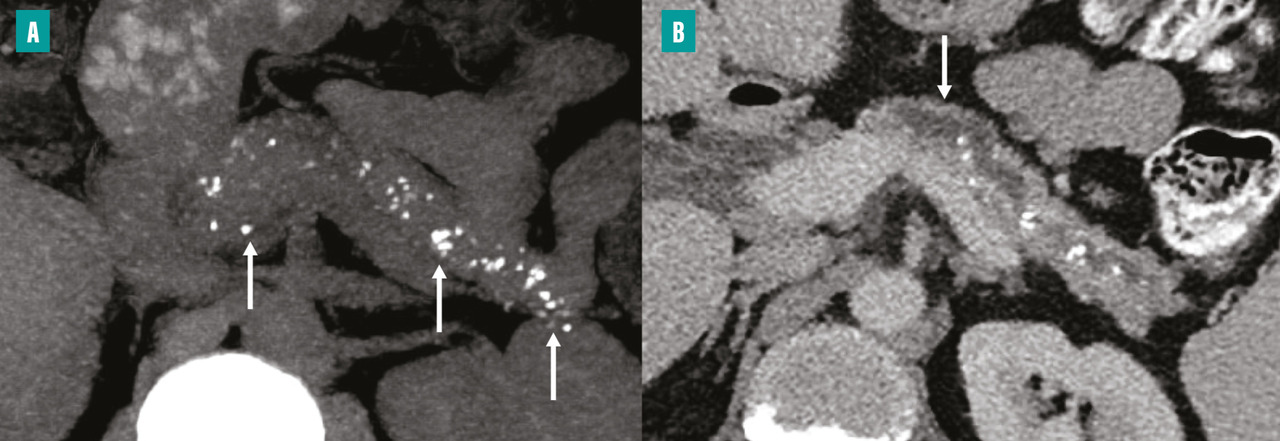

La tomodensitométrie (TDM) est l’examen initial le plus approprié en cas de suspicion de pancréatite chronique, car elle permet d’identifier des lésions caractéristiques telles que les calcifications parenchymateuses ou des conduits pancréatiques, ainsi que l’atrophie du parenchyme pancréatique. Un protocole TDM optimal comprend des acquisitions sans injection de produit de contraste, une phase artérielle pancréatique (environ 35 à 40 secondes après l’injection) et une phase veineuse (70 à 80 secondes après l’injection). Les calcifications sont facilement détectées sous forme d’hyperdensités spontanées sur les acquisitions sans injection. Elles peuvent être de taille variable. Dans les formes avancées de pancréatite chronique, la TDM peut montrer une dilatation irrégulière du conduit pancréatique principal (fig. 2) et d’éventuelles complications, notamment les pseudokystes et les atteintes vasculaires. La TDM est en revanche moins performante dans les formes précoces de pancréatite chronique, en particulier en l’absence de calcifications. La taille et le nombre des calcifications pancréatiques doivent être évalués, car le degré de calcification dans la pancréatite chronique peut refléter l’évolution et la gravité la maladie.5 La présence de grosses calcifications constitue un signe très évocateur de pancréatite chronique. Cependant, certaines calcifications parenchymateuses pancréatiques liées au vieillissement, généralement ponctiformes (de 1 à 3 mm), ne traduisent pas nécessairement une pancréatite chronique.6

Dans les formes plus avancées, la CP-IRM met en évidence une atrophie plus marquée de la glande pancréatique, avec aspect en hyposignal T1, des dilatations irrégulières moniliformes du conduit pancréatique principal et des dilatations en «  flammèches  » des conduits secondaires (fig. 3).